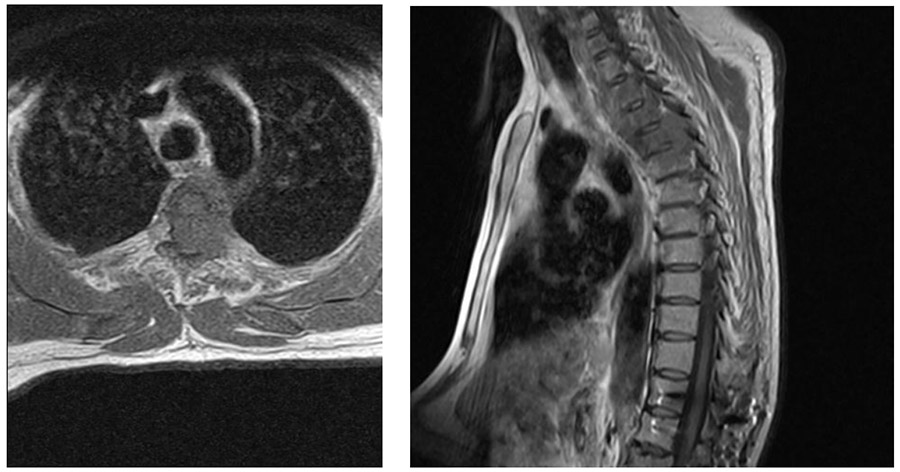

CASE 8: Lung cancer with spinal metastasis

- 47-year-old male patient

- He presented to us with complaints of progressive back pain and difficulty walking while undergoing treatment for lung cancer.

- The patient underwent surgery due to thoracic vertebral lung metastasis causing bone damage and severe spinal cord compression.

BEFORE THE OPERATION: MRI shows a mass filling almost the entire T3 vertebra and causing significant spinal cord compression.